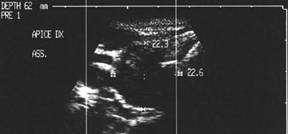

Apexul lobului drept, proiectie longitudinala si trasversala.

Femeie 58 ani. Maladia Graves in tratament cu

metimazol.

Nodul unic in apexul lobului drept, de 11x14x20mm (1,5 cc), hipoecogen, cu

contur difuz

Nu s-a efetuat citoaspiratie.

Aceeasi pacienta. La ecodoppler color - vascularizatie

periferica, avascular intralezional.

Ecopowerdoppler confirma absenta vascularizatiei interne.